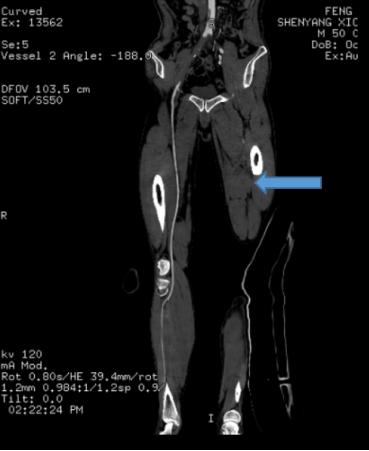

术前CT提示左侧股动脉、腘动脉以及较细血管血流不畅